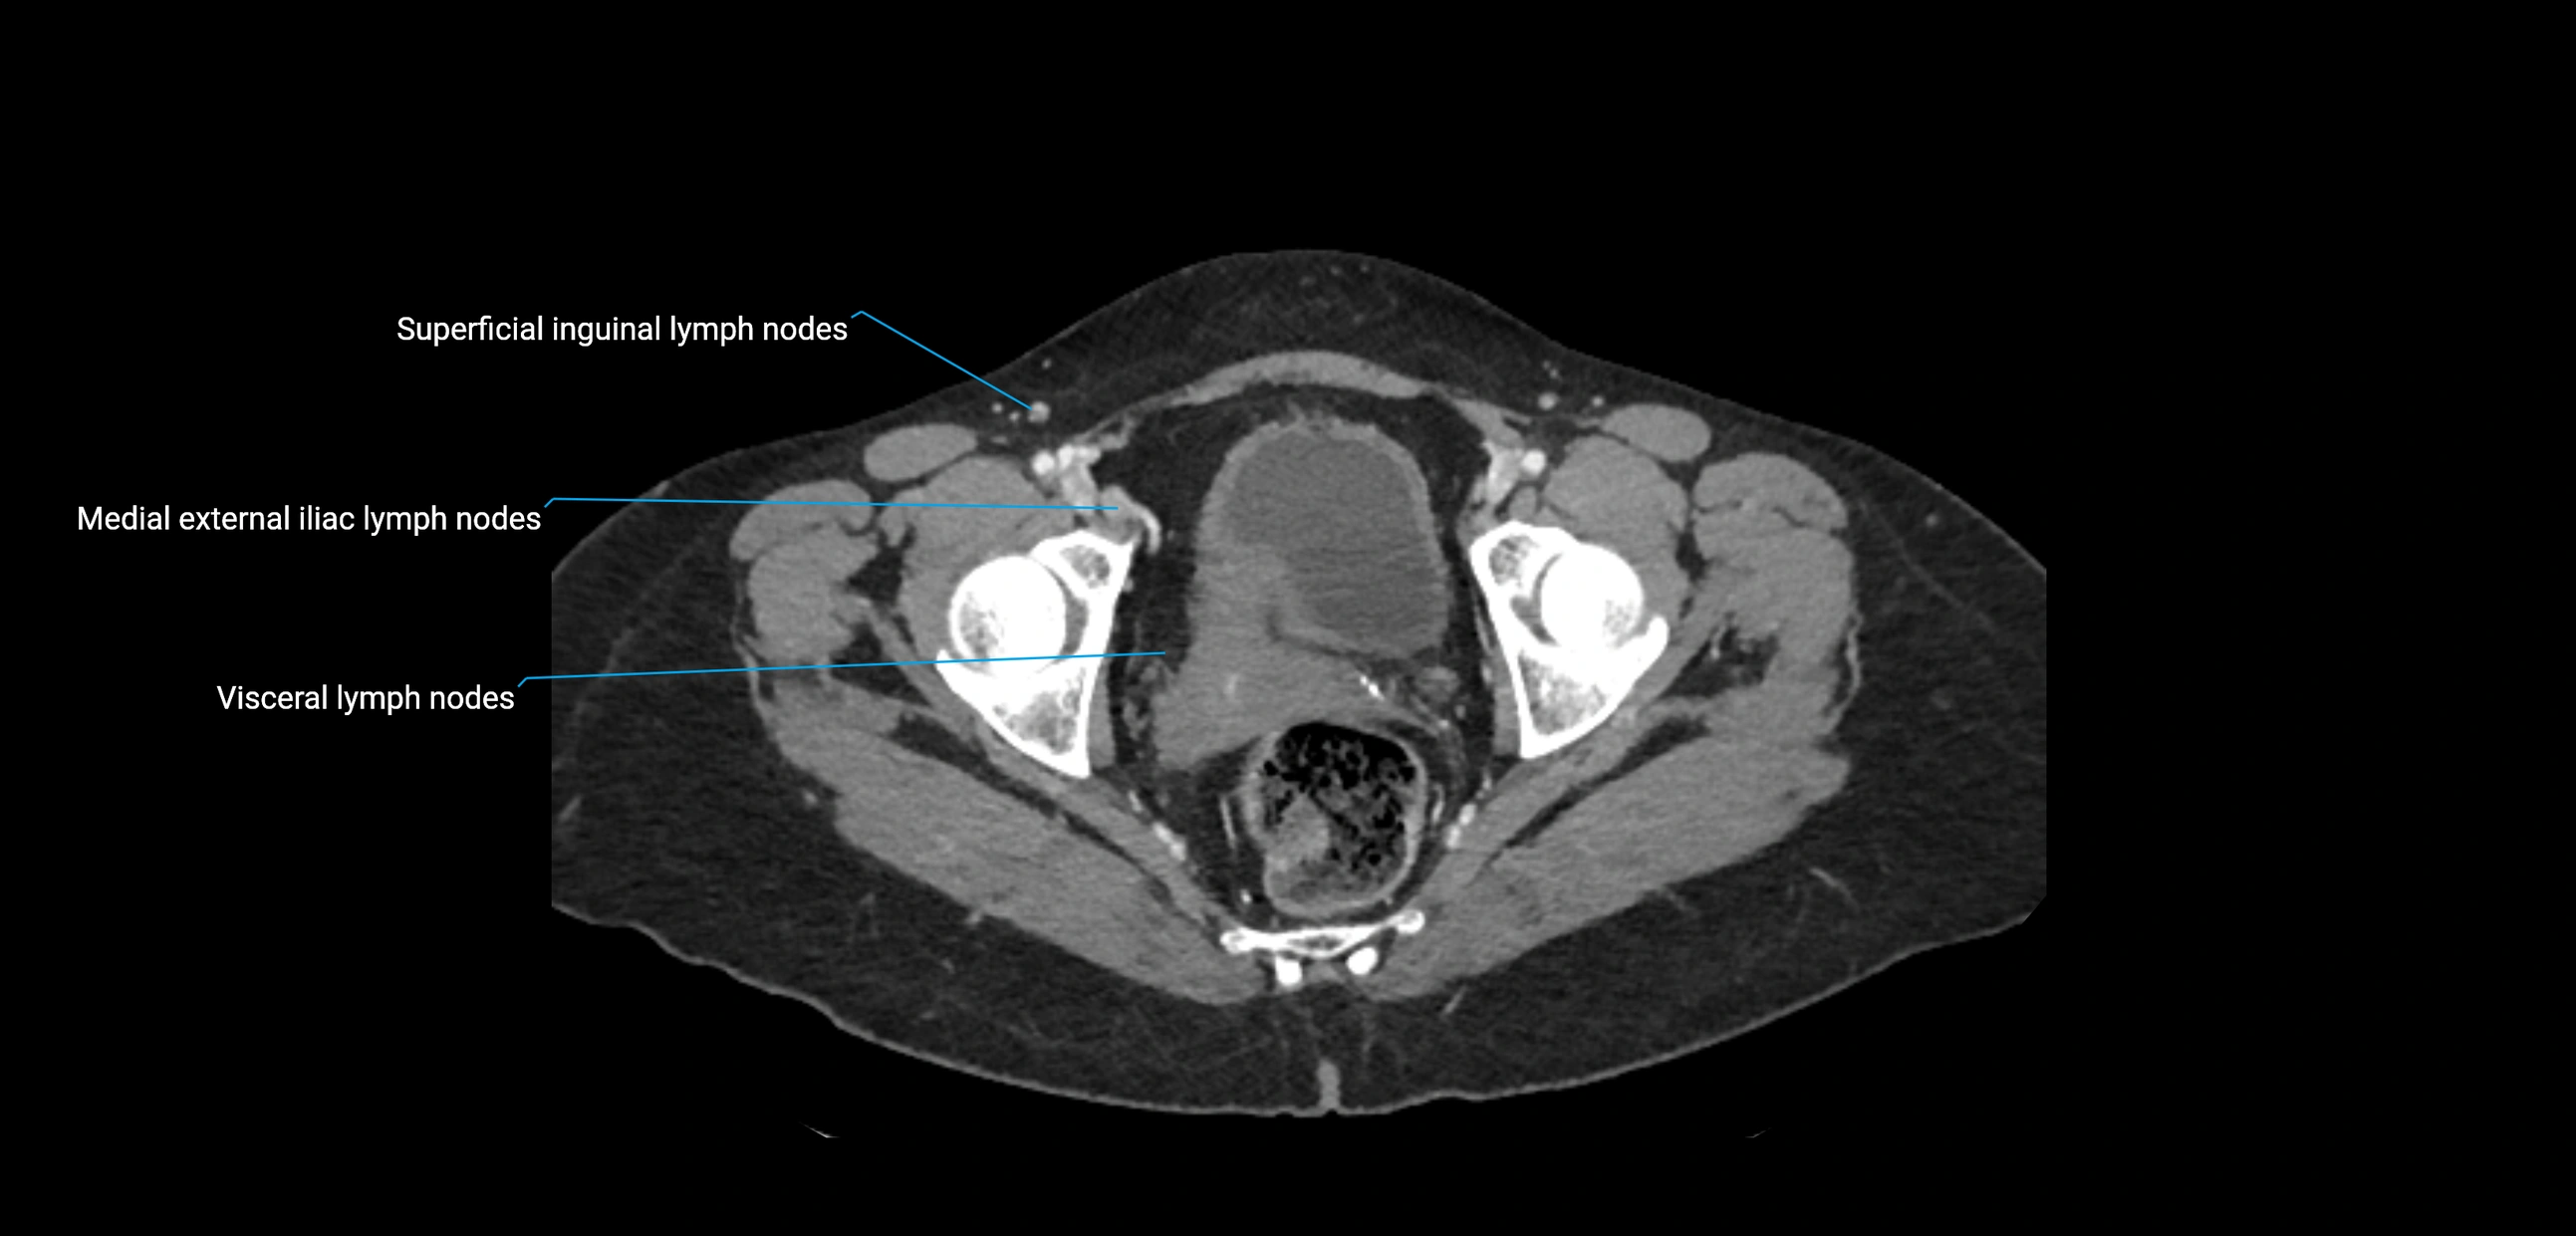

CT Appearance

CT Post-Contrast:

• Normal nodes enhance homogeneously

• Malignant nodes may show heterogeneous enhancement, central necrosis, or conglomerate formation

• Size >1 cm short axis is suspicious, though morphology and distribution are equally important

CT Venography (CTV):

• Demonstrates nodal encasement or compression of adjacent vessels (aorta, IVC, renal veins)

• Useful in staging testicular and ovarian malignancies